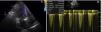

Transthoracic echocardiography showing: (A) mechanical aortic valve (21-mm Medtronic® with mild regurgitation, possibly periprosthetic; (B) elevated transvalvular gradients (maximum 51 mmHg and mean 24 mmHg); acceleration time 89 ms, left ventricular outflow tract velocity time integral/aortic velocity time integral 0.29 and area index 0.83 cm2/m2, suggestive of mismatch and/or increased flow.